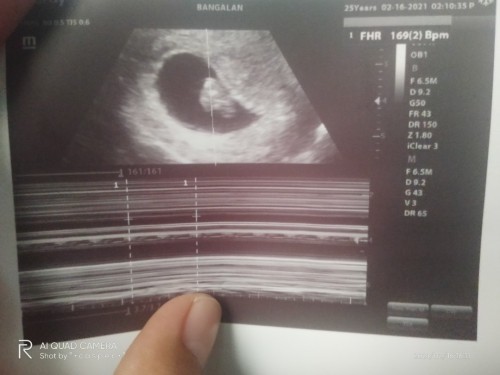

Hello little bean . π₯°

Excited na c mama mkita at lumaki ka sa tyan ko sana maging ok tayo dalawa, ππpray ππππππππ kasi, may experience na akong na kunan, 2yrs ago.